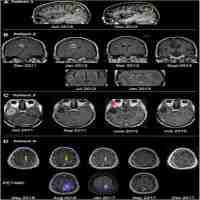

| Abstract | BackgroundBreast cancer is one of the most common malignancies worldwide and remains incurable after metastasis, with a 3-year overall survival rate of <40%.Case presentationA 40-year-old, Caucasian patient with a grade-3 estrogen receptor-, progesterone receptor-, Her2-positive breast tumor and two lung nodules was treated with intramuscular targeted immunotherapy with trastuzumab and oral tamoxifen hormone therapy, together with customized intra-tumoral oncolytic virotherapy (IT-OV) over a 17-month period. PET/CT imaging at 3 and 6 months showed increased primary tumor size and metabolic glucose uptake in the primary tumor, axillary lymph nodes and lung nodules, which were paralleled by a hyperimmune reaction in the bones, liver, and spleen. Thereafter, there was a steady decline in both tumor size and metabolic activity until no radiographic evidence of disease was observed. The treatment regimen was well tolerated and good quality of life was maintained throughout.ConclusionIntegration of IT-OV immunotherapy in standard treatment protocols presents an attractive modality for late-stage primary tumors with an abscopal effect on metastases. |